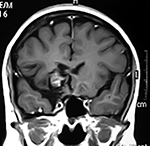

Cortes axiales en ponderación T1, cambios postquirúrgicos.

LA RMN muestra una lesión bien circunscrita frontal parasagital izquierda con edema perilesional, hiperintensa en T1 y T2, de contenido sólido y quístico, con poca captación del medio de contraste.

Se realizó craneotomía frontal para abordaje interhemisférico anterior.

Se realiza resección total de la lesión de contenido hemático oscuro-verdoso, consistente en un angioma cavernoso. La RMN postoperatoria se observa solo la brecha quirúrgica sin evidencia de lesión.

Figura 4:

Imágenes prequirúrgicas y postquirúrgicas de lesión multiloculada del caso 9.